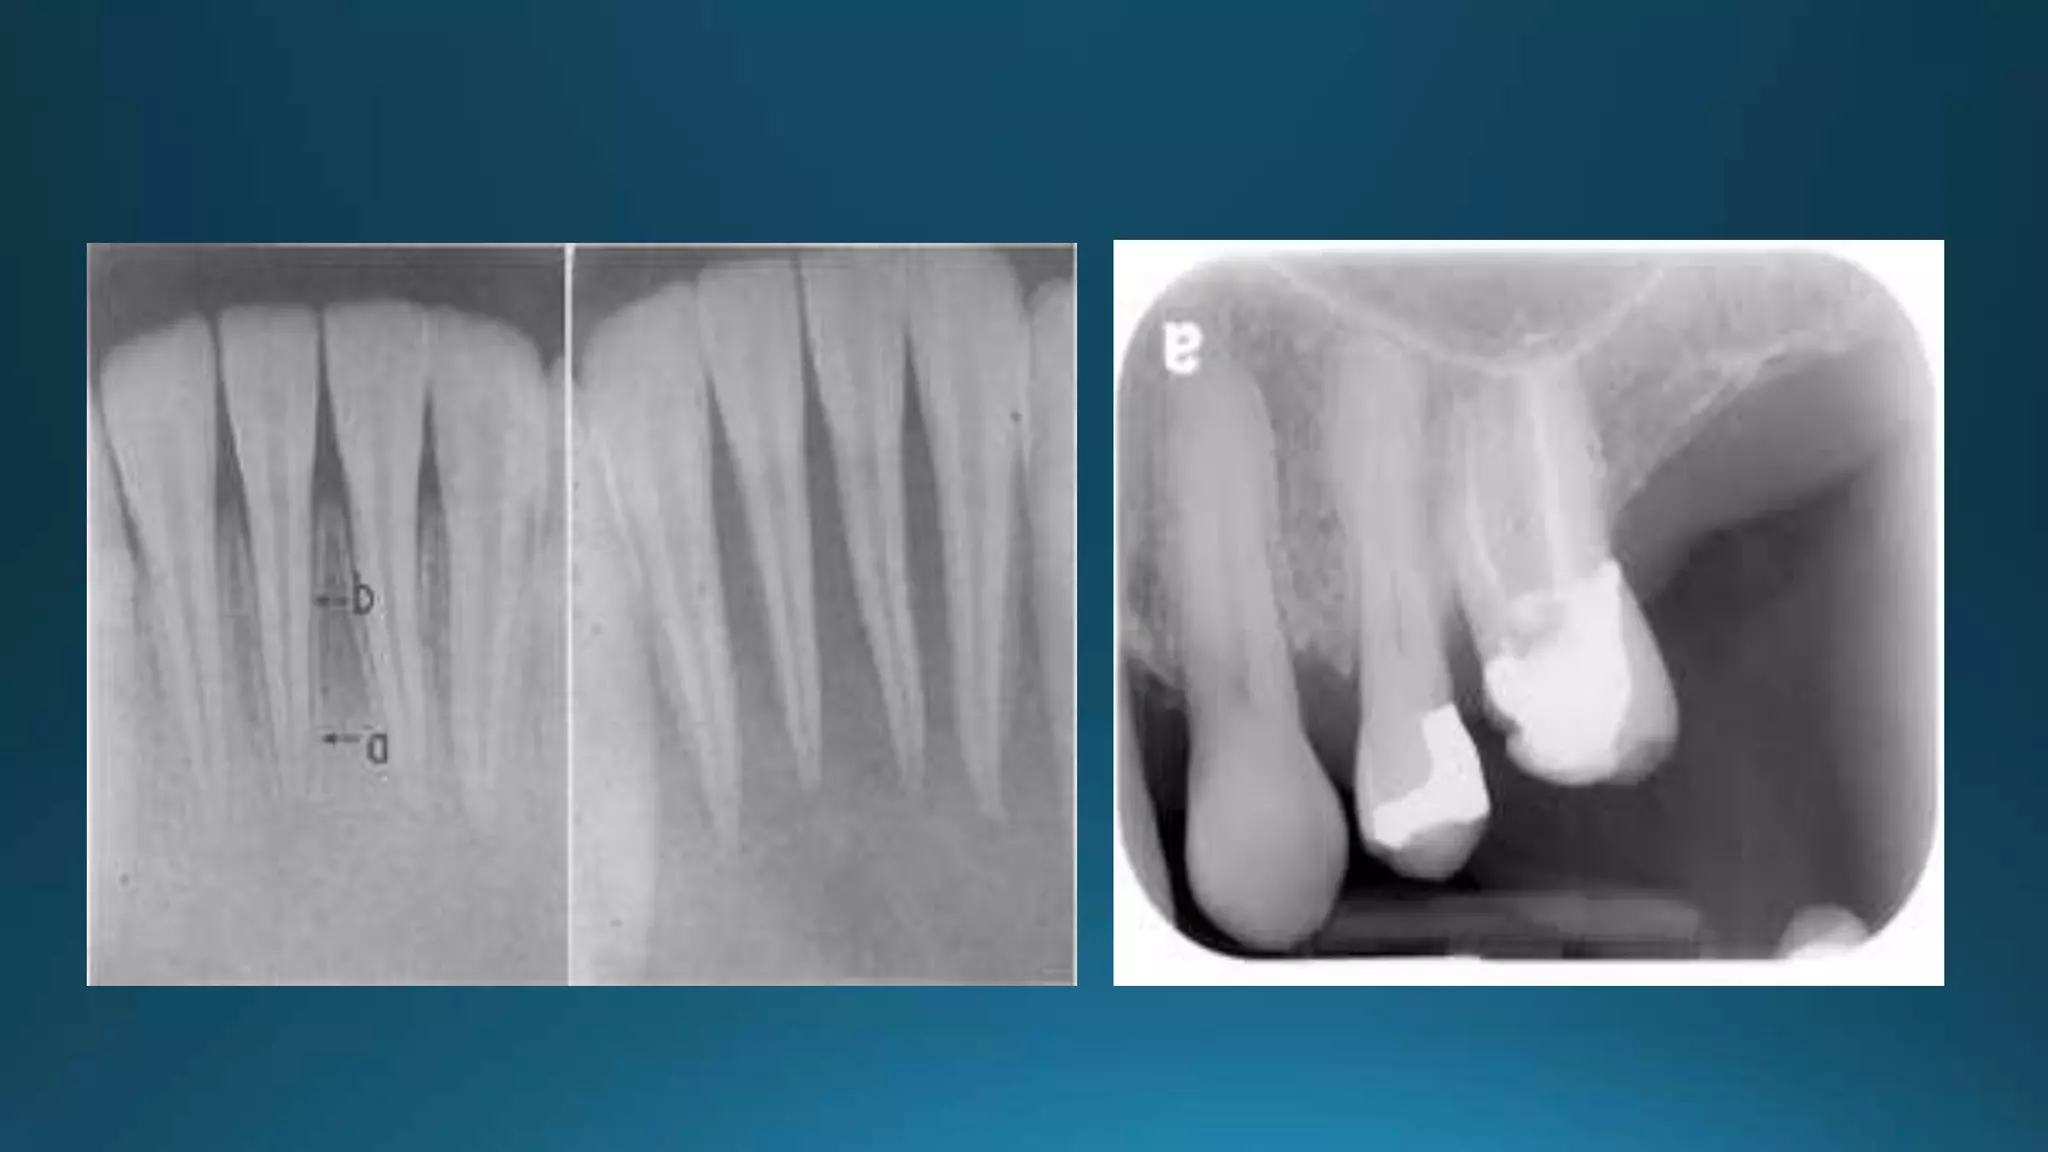

Mandibular first premolar with three separate roots trifurcating at midroot.

B, Radiograph of three views.

Small canals diverging from the main canal create a configuration that is very difficult to prepare and obturate

biomechanically

Root section of a premolar showing a ribbon-shaped canal system

Diagrammatic representation of Kartal andYanikoglu’s canal configurations

Mesial view of a mandibular premolar with a

Vertucci typeV canal configuration.

The lingual canal separates from the main canal

at nearly a right angle.

B,This anatomy requires widening of access in

a lingual direction to achieve straight-line

access to the lingual canal.

crown down instrumentation.